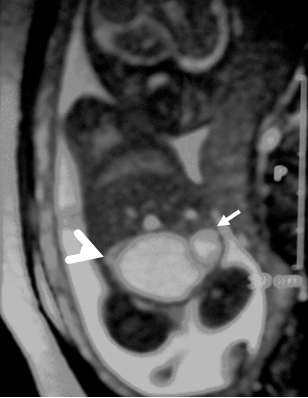

In the axial plane, besides type IV SCT (big arrow head) and hydrometrocolpos (white arrow); both kidneys (white asterix) appeared in normal loca¬tion and anatomy (Fig. 4). In the coronal plane fetal bladder (black empty arrow) was noticed (Fig. 5).

Figure 5: Fetal MRI coronal plane. |